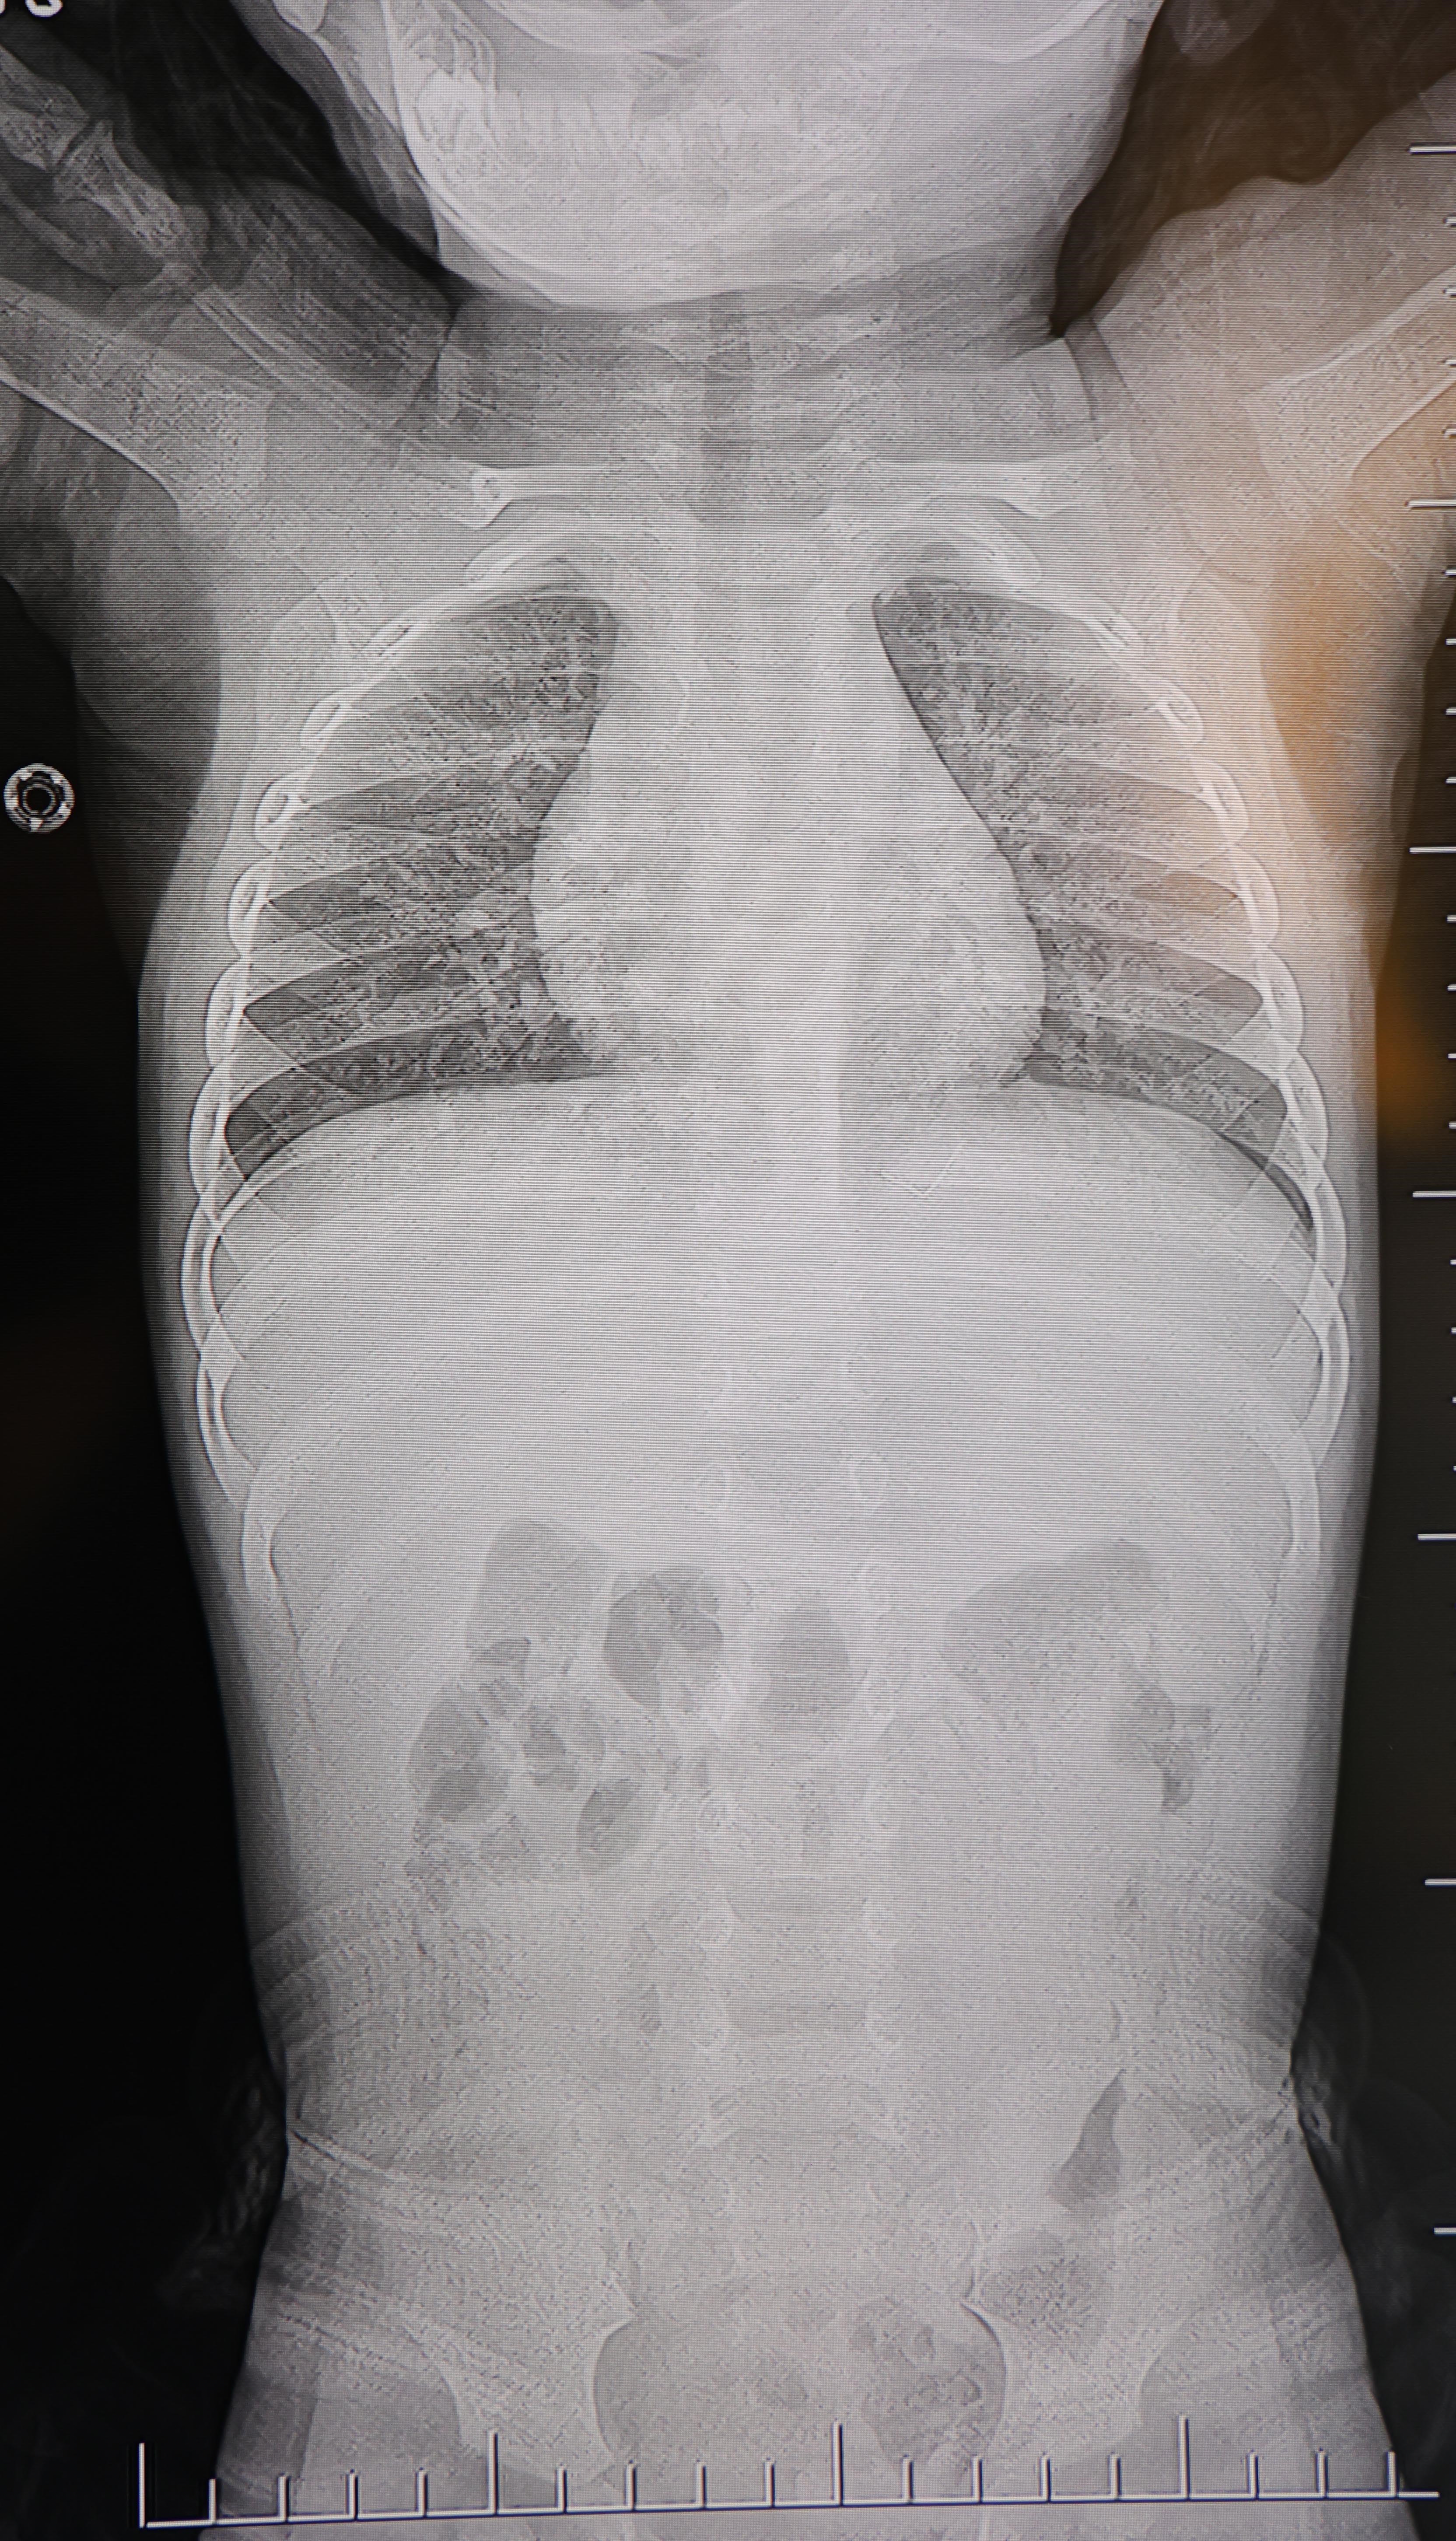

Baba Poyraz, bir gün acil serviste yapılan kontrollerde bebeğin belinde yabancı cisim olduğunu, çekilen filmlerde ise "L" şeklinde zımba teli tespit edildiğini söyledi. Çeşitli hastanelere yönlendirildiklerini anlatan baba, uzun süre müdahale edilmediğini, daha sonra özel bir hastanede yapılan operasyonla zımba telinin çıkarıldığını kaydetti.

"Filmlere baktılar 'L şeklinde zımba teli var, alınması lazım' dediler"

Poyraz, bebeğin doğduktan sonra sarılık diyerek kuvöze alındığını belirterek, "Bir hafta orada yattı. Sonra çıkardılar, eve getirdik. Eve geldikten sonra gece gündüz ağlaması hiç durmadı. Tekrar hastaneye götürdüm. Kaşınıyordu, bir hafta banyo yaptıramadık. Sonra duş aldırdım, bağırması daha da arttı. Belini açtık, sırtına baktık, bir şey var mı diye kontrol ettik, görünürde yoktu. Hastaneye götürdük, şurup verdiler. Aylar geçti. Daha sonra acilde bir doktor çocuğumun belinde yabancı cisim olduğunu söyledi. 184'ü aradım, şikayette bulundum. Başhekim yardımcısının yönlendirmesiyle tomografi çekildi. O zaman belinde zımba teli olduğu netleşti. Başka bir hastaneye götürdük, 'riskli, 8 yaşına kadar alınamaz' dediler, geri gönderdiler. Eve geldikten üç gün sonra oğlum bayıldı. Kardeşimle özel hastaneye götürdük. Orada filmlere baktılar, 'akciğere doğru gidiyor, L şeklinde zımba teli var, alınması lazım' dediler" dedi.